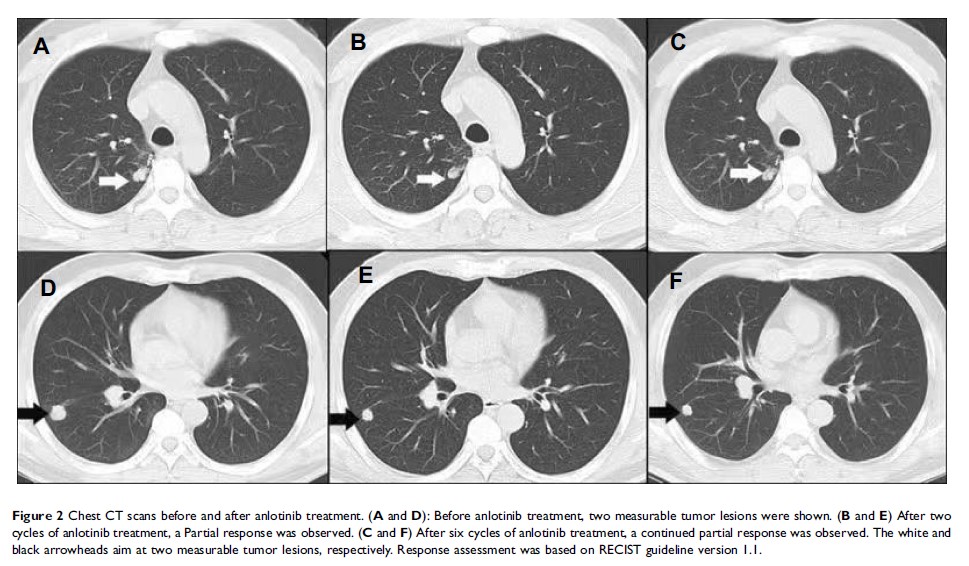

- 作者:Shujie Song, Ping Sui, Minmin Li, Liangming Zhang, Dengjun Sun